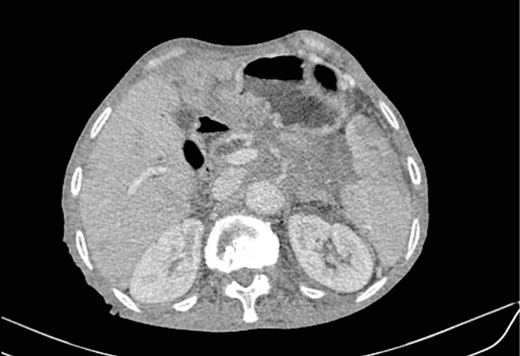

Mr. B. is a 59-year-old patient with no notable pathological history, presenting with melenas associated with marked weight loss. A fibroscopy revealed a thickened and ulcerated gastric mucosa. Abdominal and pelvic CT scans revealed a tissue process in the body and tail of the pancreas invading the splenic hilum, adjacent vessels ans gastric wall, measuring 11 cm long (Fig. 5). A caudal spleno-pancreatectomy enlarged to the colon, omentum and stomach was performed. Macroscopically, the tumor had a grayish–white appearance, poorly limited and indurated on palpation. Histologically, it was a well-differentiated, keratinizing squamous cell carcinoma of the tail of the pancreas (Figs 6 and 7), infiltrating the splenic hilum, gastric wall and colon.

Low enhancing mass at pancreatic body and tail with internal necrotic changes. The mass encases the AMS and its branches and encases splenic vessels. Loss of the fat plane between the mass and adjacent spleen.

HE section showing nests and sheets of polygonal cells surrounded by fibrotic desmoplastic stroma (x100).